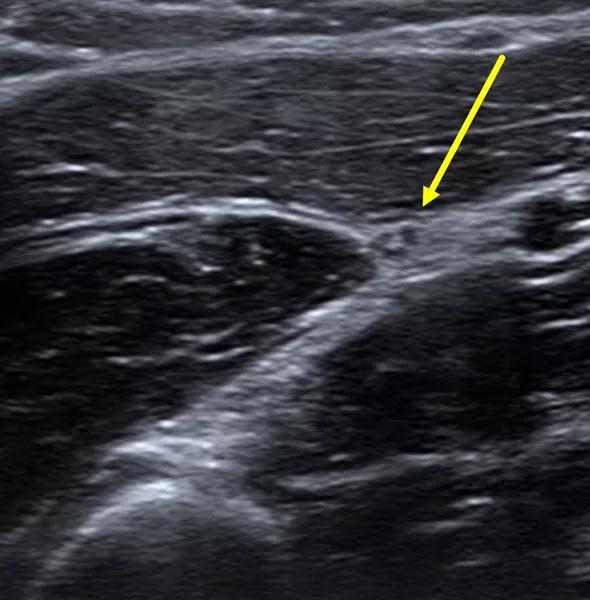

Conservative management — including NSAIDs, splinting and physical/occupational therapy — failed to relieve the patient’s symptoms, so he elected to undergo an ultrasound-guided perineural steroid hydrodissection (Figure 2). After one month, the patient reported a 75 percent subjective improvement in symptoms with only mild modification of activity.

Figure2. Transverse sonographic image demonstrating perineural hydrodissection with a 25-gauge needle (red arrows) of the superficial branch of the radial nerve (yellow arrow).